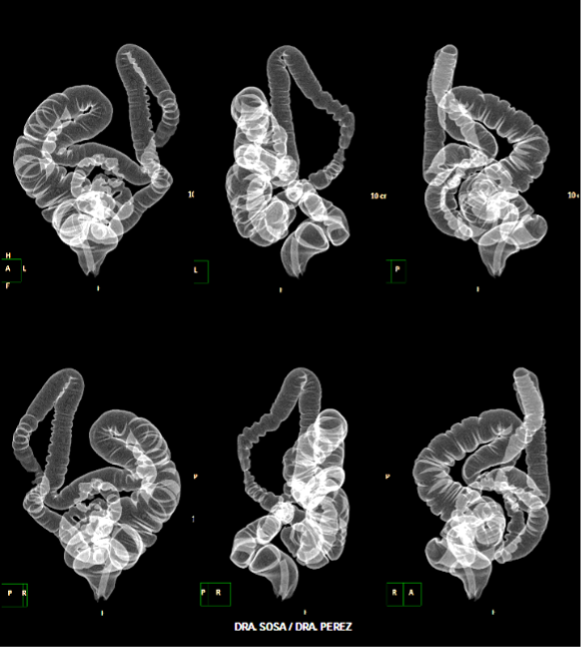

| POSPROCESAMIENTO DE IMÁGENES TOMOGRÁFICAS DE COLON PARA DIAGNOSTICAR CASOS DESAFIANTES. Autor: Dr. SERGIO MARTINEZ-MILLAN - Volumen 79 (4) GEN 2025 | |